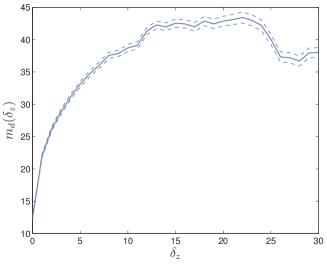

For the brain database, an interesting result is that the distance between brain slices that are physically close is shorter than the distance between slices wide apart in the brain. In other words, if we consider the brain MRI as a volumetric image for which each slice in the database is the result of fixing to some value, then the expectation of the distance between two slices separated along the axis by a distance ,

| (3) |

is an increasing function of for sufficiently close to zero. Fig. 4 shows the evolution of (with two dashed curves providing the 99% confidence interval on estimation) computed over the 100 brain slices rotated and scaled. The expectation of the distance is indeed increasing for . This means that the distance between ISH truly reflects the difference between visual contents. The MRI was indeed taken with a resolution of 1mm for which visual contents of contiguous slices are very close, as depicted in Fig. 4. The false positive pairs of images are therefore more likely to be adjacent slides which are visually close than totally different slides.